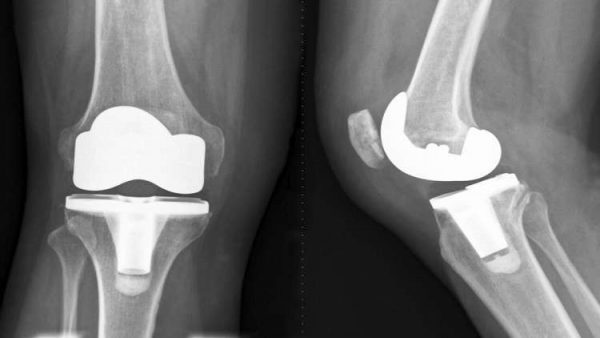

الحكمة – متابعة: سجل علماء من جامعة تومسك الروسية للكيمياء براءة اختراع جديدة تعتمد على النباتات البحرية لتطوير نسيج عظمي اصطناعي.

وفي البيان الصادر عن الجامعة مؤخرا جاء أن “علماء في الجامعة تمكنوا من تطوير طريقة جديدة كليا لتركيب مادة الهيدروكسيباتيت المستخدمة في مجال الجراحة التجميلية وترميم العظام. اعتمدت الطريقة على الجيلاتين النباتي المستخرج من بعض أنواع الطحالب البحرية”.

وأضاف البيان أن “أهم ما في الأمر أن العلماء تمكنوا من استخدام الأشعة الكهرمغناطيسية لتصنيع المسحوق الجديد، ما يؤثر بشكل إيجابي على بنية النسيج الاصطناعي الذي يحوي هذا المسحوق والمخصص لترميم العظام، حيث سيتمتع النسيج ببنية مسامية تساعد على ترميم العظام بشكل أسرع”.

من جانبها قالت البروفيسور نتاليا كوروتشينكو، إحدى المشرفين على الدراسات الجديدة في الجامعة: “استخدام الأشعة الكهرمغناطيسية يوفر توزيعا متساويا لدرجات الحرارة على كافة جزيئات المواد التي يتكون منها المسحوق، الأمر الذي يجعل المسحوق أكثر تجانسا، فضلا عن أن استخدام هذه الأشعة يوفر الكثير من الوقت والتكاليف على عكس الطرق العادية التي تعتمد على الأفران الحرارية لتجفيف المساحيق. الأمر المثير أننا نستطيع أيضا تعديل بنية المسحوق بإضافة أيونات العناصر المعدنية كالفضة التي ستجعل المسحوق يتحلى بخصائص مضادة للجراثيم، مما يسرع من عملية ترميم العظام”.